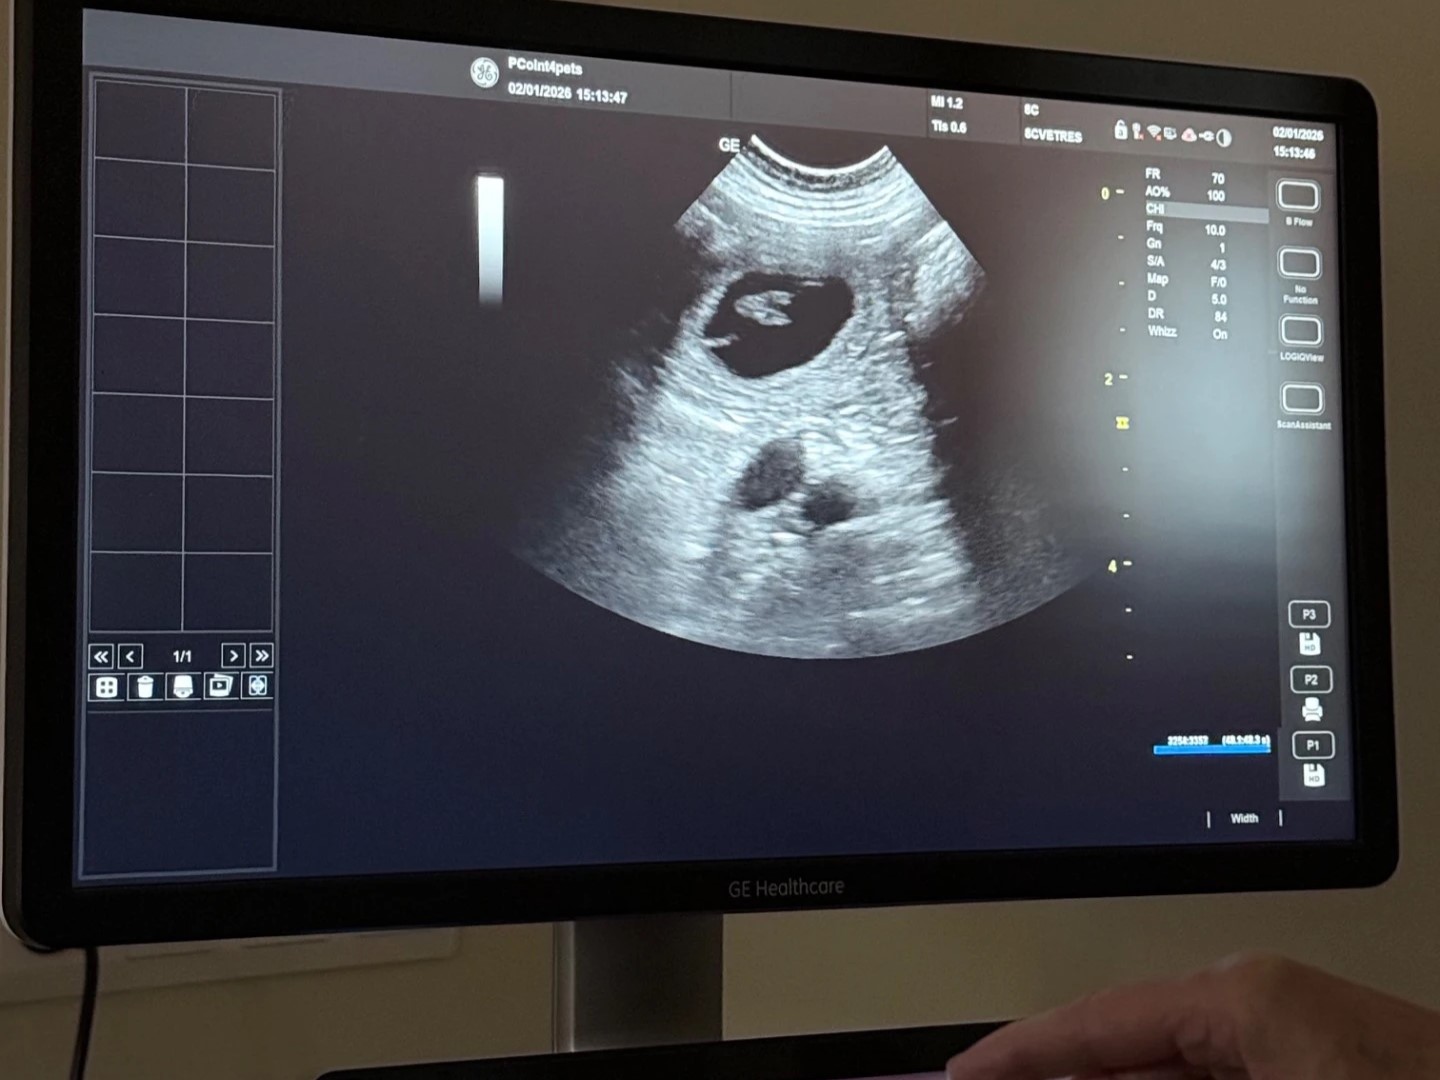

2.1.2026 Sonogratické vyšetření nám potvrdilo, že Fidorka čeká štěňátka.